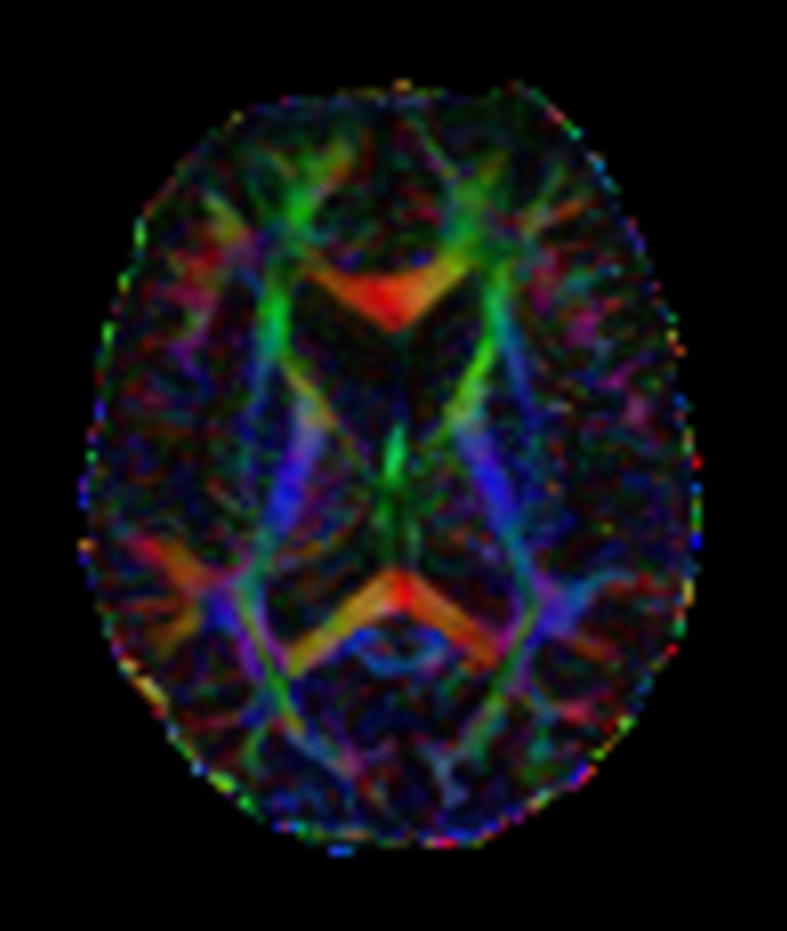

Patient with a lesion in the cerebellum. The ExamCard includes Compressed SENSE to accelerate the entire exam and techniques for motion reduced imaging (MultiVane XD), 3D imaging to acquire high resolution data in multiple directions, 3D susceptibility weighted imaging (SWIp), angiography sequences (Time-of-Flight and Contrast-Enhanced MRA with both arterial and venous phases), DTI with MultiBand SENSE to acquire a high number of diffusion directions in a short scan time and EPIC Brain to bring down any residual distortion.

DTI b800 15 directions (FA map)

DTI b800 MultiBand SENSE 32 directions

DTI b800 MultiBand SENSE 32 directions (FA map)